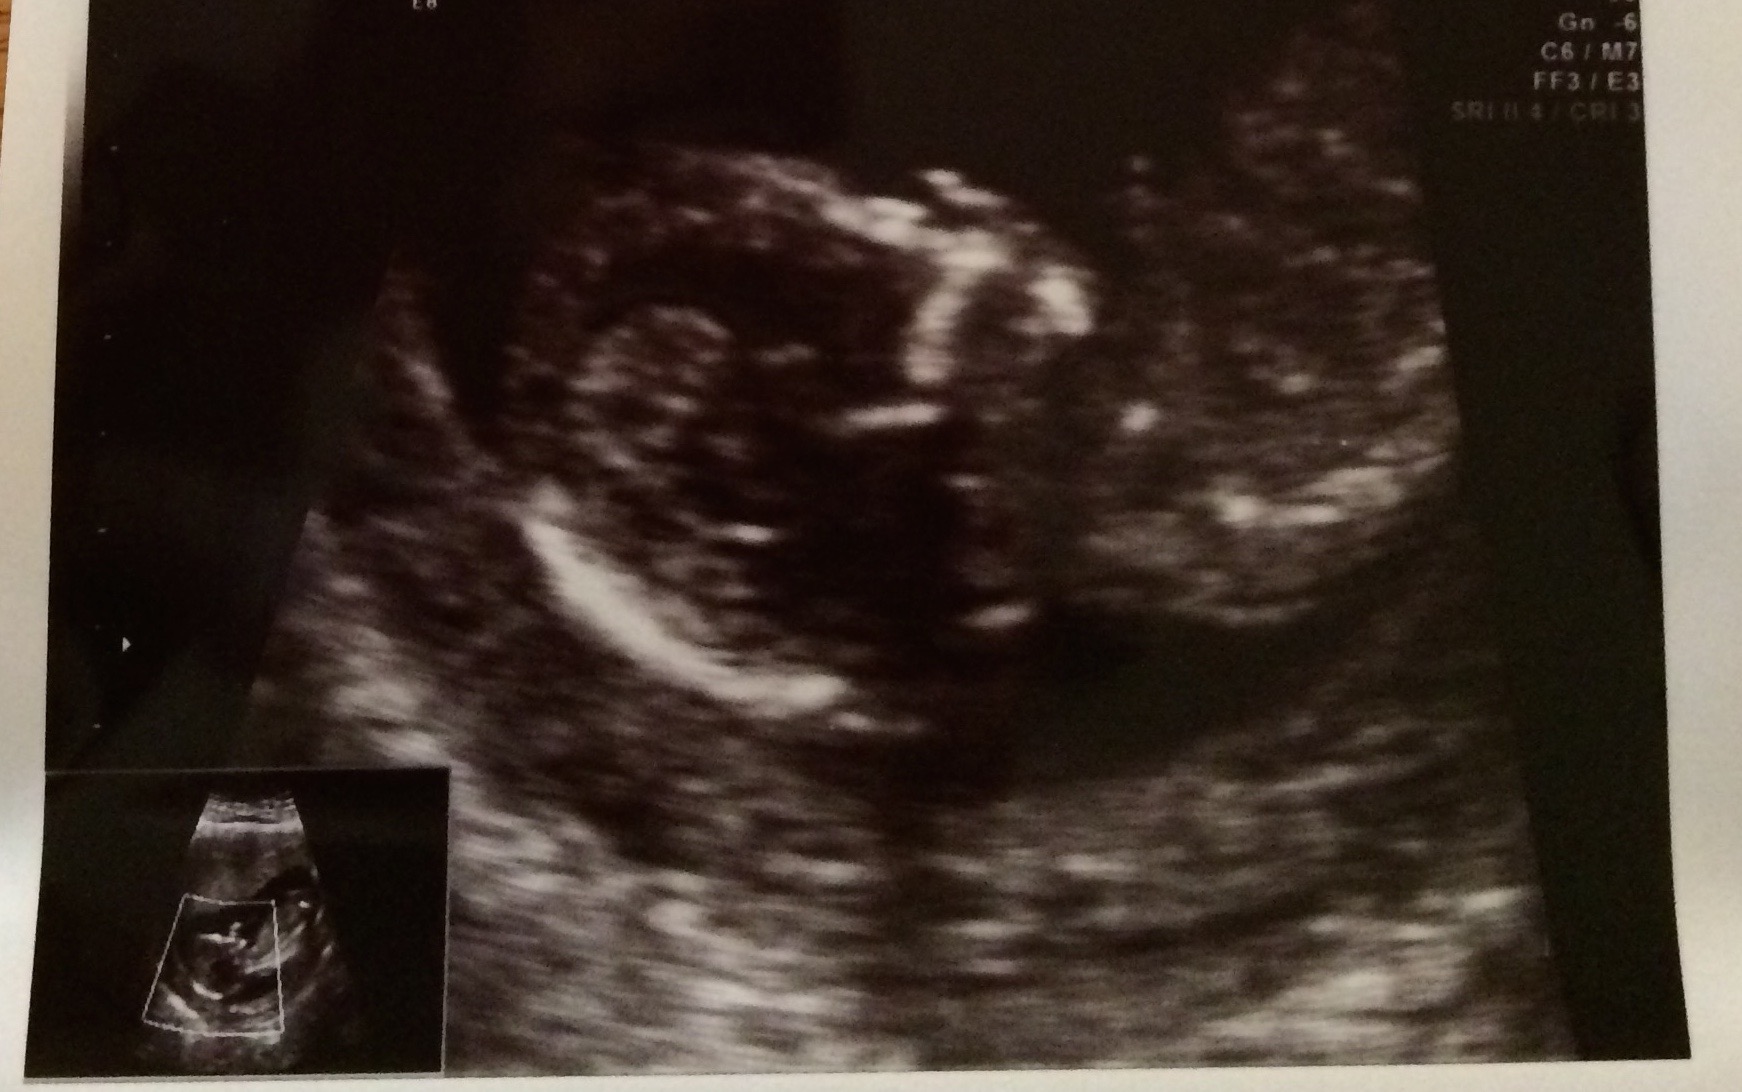

15w2d -- little boy is camera shy! He's laying with his arm curled under his face. His face resembles a Halloween mask! Lol super active with a heartbeat going from 144-151. Stretched out with his feet on one side, and head on the other.